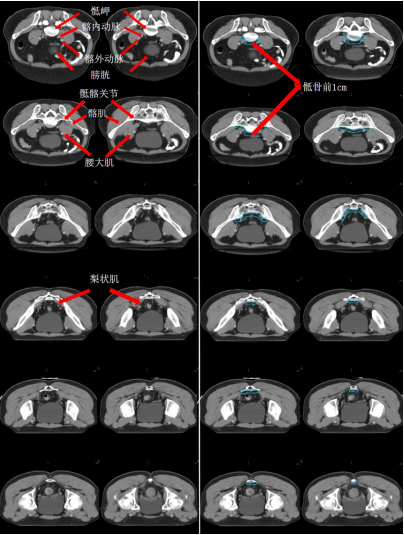

i) 高危復(fù)發(fā)區(qū)合集圖(CT 層厚 0.5 cm,俯臥位)(圖 14)。下表 示出高危復(fù)發(fā)區(qū)顏色。

表 直腸癌高危復(fù)發(fā)區(qū)顏色

圖 14 直腸癌高危復(fù)發(fā)區(qū)合集圖